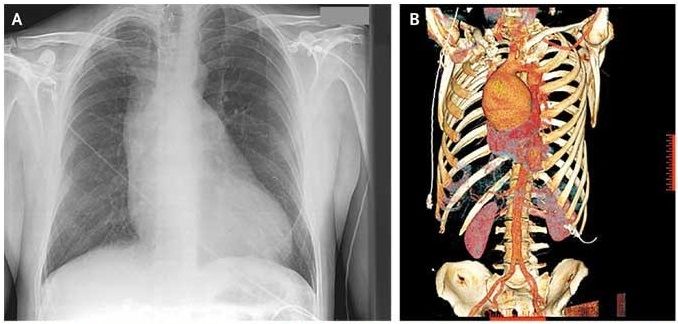

Auscultation of the precordium was notable for an aortic regurgitant murmur. Electrocardiography showed left ventricular hypertrophy. Chest radiography revealed a widened mediastinum (Panel A). 3-D reconstruction computed tomographic angiography of the chest showed a 9.5-cm ascending aortic aneurysm (Panel B).

The patient underwent an ascending aortic root replacement, during which the aneurysm was visible through the median sternotomy, and a Dacron graft was successfully placed. The patient had a full and uneventful recovery.